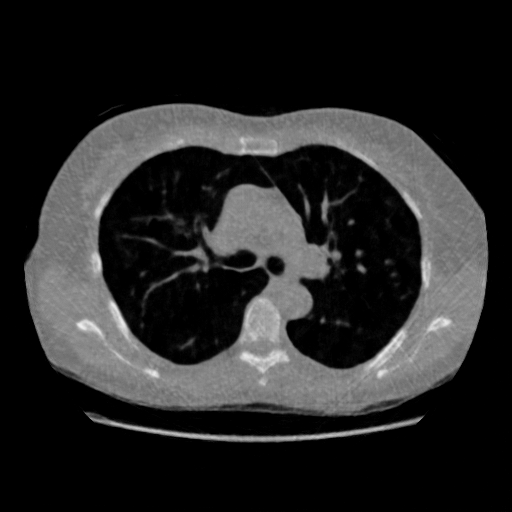

IV-D Limited-Angle CT Reconstruction

To test the proposed framework’s performance on limited-angle reconstruction, we redo the experiment in the above section with the angular range changing from to for parallel-beam geometry and to for fan-beam geometry, one projection per degree. The experiment results are shown in Fig.6. Also, the ground truth and the limited-angle CT reconstruction results of different methods are shown in the row of Fig.7 (parallel-beam, LIDC-IDRI dataset), and Fig.8 (fan-beam, LIDC-IDRI dataset).

SNR/SSIM

16.31dB/0.55

20.83dB/0.83

13.37dB/0.61

16.65dB/0.79

13.40dB/0.73

16.85dB/0.65

22.47dB/0.78

14.25dB/0.63

22.99dB/0.62

19.51dB/0.56

(a) Ground Truth

30.15dB/0.85

(b) ASD-POCS

39.35dB/0.94

(c) RBP-DIP

27.10dB/0.78

(d) DIP

23.88dB/0.65

(e) MED50

20.59dB/0.60

(f) RED-CNN